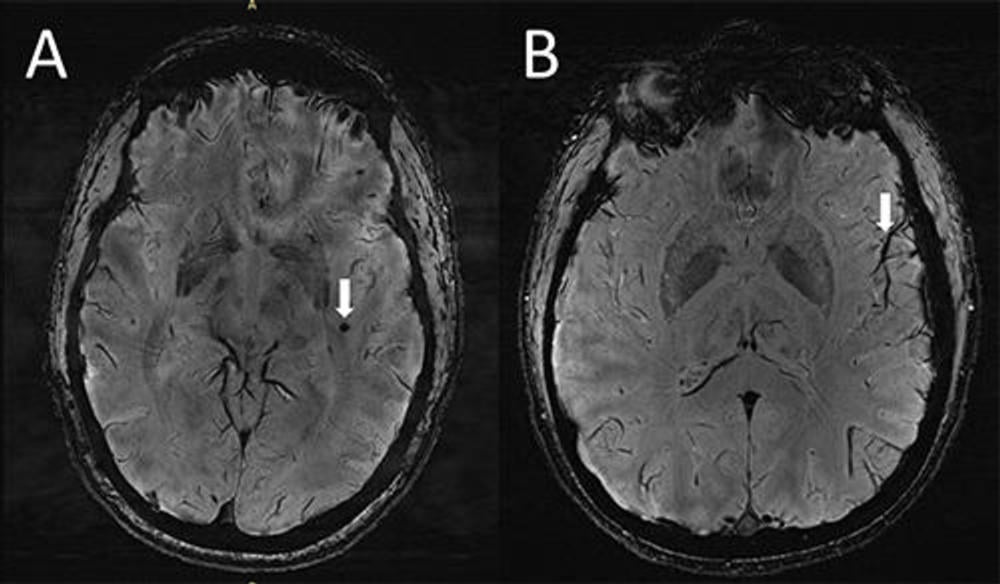

Kolejny etap badań polegał na wykonaniu obrazowania metodą rezonansu magnetycznego w wysokiej rozdzielczości. Pole magnetyczne było ponad dwukrotnie silniejsze niż w przypadku większości szpitalnych urządzeń, co przełożyło się na wyższą jakość uzyskiwanych obrazów. To z kolei oznaczało możliwość dostrzeżenia zmian w mózgu, które do tej pory pozostawały niezauważone.

Do jakich wniosków doszli autorzy? Przede wszystkim przestrzenie okołonaczyniowe okazały się zauważalnie większe u osób cierpiących na migreny. Poza tym naukowcy zwrócili uwagę na zmiany określane mianem hiperintensywności substancji białej. W przypadku obu “migrenowych” grup nie było większych różnic, choć pacjenci regularnie doświadczający bólu cechowali się nieco większymi rozmiarami zmian.